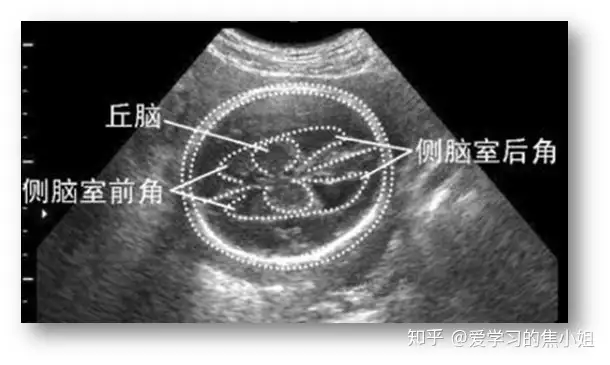

五、侧脑室增宽(VM)

侧脑室位于大脑半球的深部,左、右各一,呈“C”形室腔,内衬室管膜,腔内充满脑脊液。分为中央部、前角、后角、下角,并以室间孔与第三脑室相通。

正常:侧脑室体部宽度≤10mm,平均7mm。

侧脑室扩大:直径10mm以上。轻度脑室扩大(MVM)定义为10至15毫米之间。常有胎儿脑积水的表现。

脑积水:指伴有脑脊液压力增加的侧脑室增宽者,常伴有头围异常。分为梗阻性脑积水和交通性脑积水。VM原因:脑脊液回流异常、神经元移行障碍、破坏性进程。重度的侧脑室增宽可有脑脊液动力改变、脑组织结构异常和脑组织破坏。